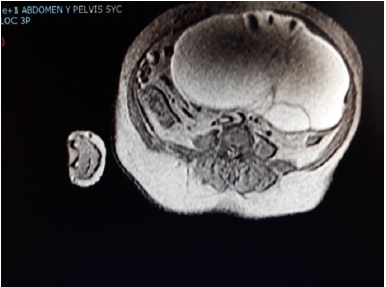

El informe de la RM abdominopélvica con gadolinio iv (cortes axiales Spin Echo-SE potenciados en T1 y Fast Spin Echo potenciados en T2 sin gadolinio y cortes axiales SE potenciados en T1 con gadolinio) revela una voluminosa imagen quística multitabicada con nódulos murales, que ocupa casi la práctica totalidad del hemiabdomen izquierdo llegando a pelvis menor (fig. 1 y 2). No se aprecia realce de la lesión tras la inyección de contraste ni tampoco imagen clara de núcleo sólido. La lesión es sugestiva de cistoadenocarcinoma de ovario izquierdo. Se aprecia contenido hematometra en cavidad uterina.